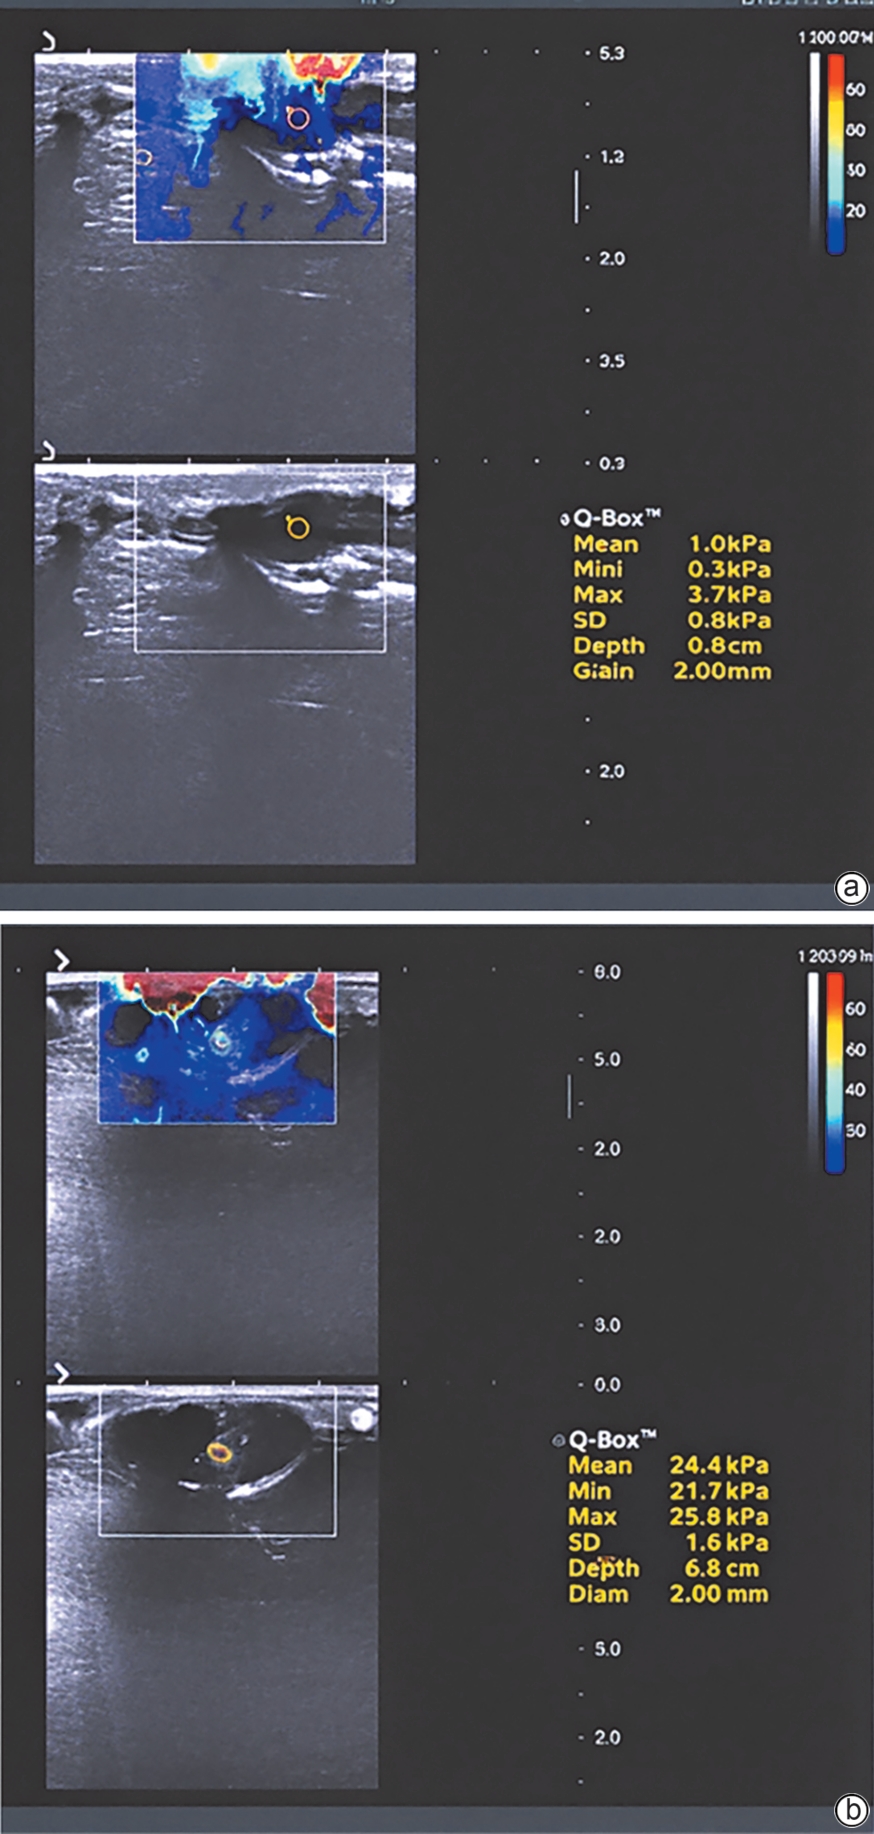

磁共振弹性成像在代谢相关脂肪性肝病肝纤维化评价中的应用

张子毅, 尤红, 佟小非

2026, 42(3): 683-689. DOI: 10.12449/JCH260325

摘要(135) HTML (29) PDF (675KB)(49)

摘要:

磁共振弹性成像(MRE)已成为代谢相关脂肪性肝病(MAFLD)中诊断和分期纤维化的重要工具,其具有较高的诊断准确性,能够有效评估MAFLD患者肝纤维化的动态变化及其长期预后。此外,MRE在代谢相关脂肪性肝炎新药研发的患者筛选与疗效评估中也显示出广泛潜力。本文综合分析了MRE在评估MAFLD患者肝纤维化方面的潜在价值,并探讨了其在临床实践中的优势和未来的发展方向。